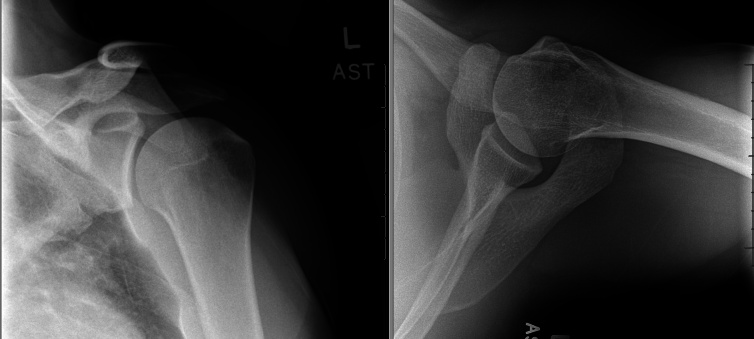

本病例报告和技术说明详细介绍了采用单切口腋窝入路和全缝合锚定张力滑动技术成功修复高需求运动员背阔肌肌腱断裂的手术。患者是一名38岁的竞技运动员,在斯巴达比赛中受伤,表现出严重的功能限制,包括肩部无力和运动和专业活动中的表现受损。临床和影像学结果证实了完全性LD肌腱断裂,并伴有6厘米的内陷和相关的大圆肌部分撕裂。手术修复包括肌腱活动,肱骨足迹的准备,以及在张力滑动结构中用全缝线锚钉固定。术后,患者接受了量身定制的康复方案,在7个月后几乎完全恢复到损伤前的功能。这种创新的技术有很多优点,包括美容切口、手术并发症最小化以及熟悉运动外科医生的技术。与皮质钮扣相比,全缝线锚钉避免了金属植入,减少了骨质流失,简化了手术过程。虽然有效,但该方法需要技术专长,特别是在减轻神经血管风险方面。本报告强调了该方法治疗高需求运动员LD肌腱断裂的有效性和可重复性。进一步的生物力学和临床比较是必要的,以完善手术适应证和优化结果。

This case report and technical note details the successful surgical repair of a latissimus dorsi (LD) tendon rupture in a high-demand athlete using a single-incision axillary approach with an all-suture anchor tension slide technique. The patient, a 38-year-old competitive athlete, sustained the injury during a Spartan Race, presenting with substantial functional limitations, including shoulder weakness and impaired performance in athletic and professional activities. Clinical and imaging findings confirmed a complete LD tendon rupture with 6 cm of retraction and associated teres major partial tearing. Surgical repair involved tendon mobilization, preparation of the humeral footprint, and fixation with all-suture anchors in a tension slide configuration. Postoperatively, the patient underwent a tailored rehabilitation protocol, achieving near-complete return to preinjury function by 7 months. This innovative technique offered advantages, including cosmetic incision, minimized surgical morbidity, and familiarity with sports surgeons' techniques. The all-suture anchors avoid metal implants, reduce bone loss, and simplify the procedure compared to cortical buttons. Although effective, the approach requires technical expertise, particularly in mitigating neurovascular risks. This report underscores the efficacy and reproducibility of this method in treating LD tendon ruptures in high-demand athletes. Further biomechanical and clinical comparisons are warranted to refine surgical indications and optimize outcomes.